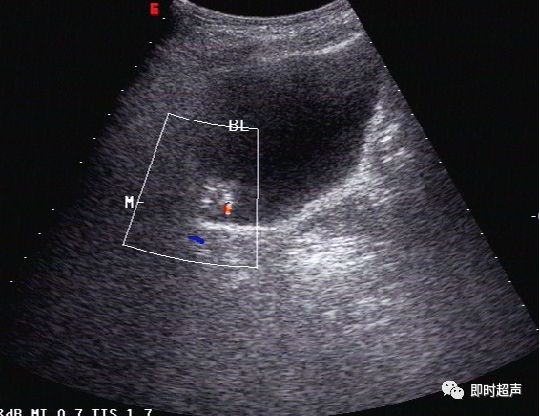

超声表现:

- 膀胱后壁可见团状低回声,向腔内隆起

- 膀胱壁局限性增厚,黏膜光滑完整

- CDFI:病变内无血流信号

二维 CDFI

膀胱左侧壁3点处团状等回声(箭头)

CDFI:内无血流信号